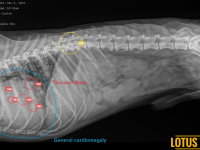

1 Radiology

Radiology Pictures